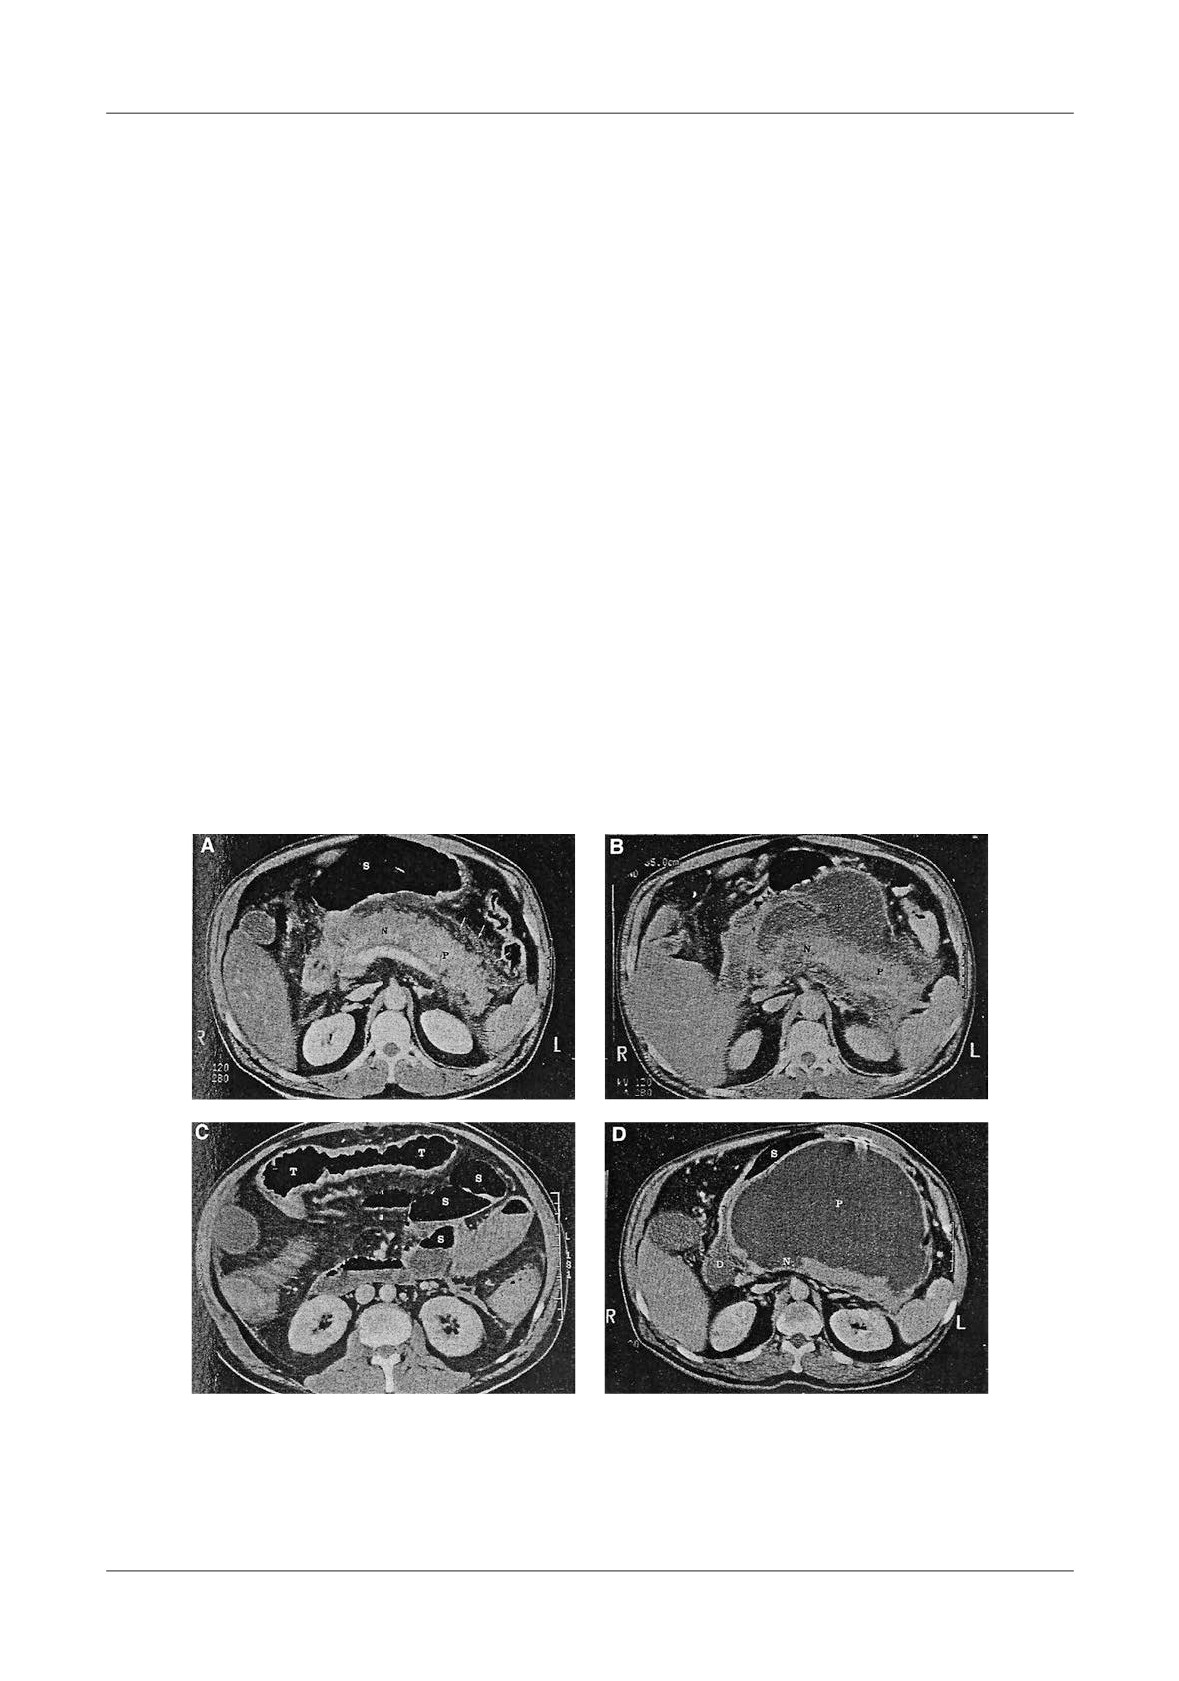

Figure 1. Pancreatic necrosis with the development of a pseudocyst, ileus and colonic in ltration in a 38

-year-old man. A-At admission the CT- shows enlarged pancreas and peripancreatic in ammation,  uid

(N=necrosis, P=pancreas, S=stomach), B-Lique ed necrosis nine days later with partially encapsulated

uid collection in the lesser sac, C-Dilated small bowel loops, with a haustral transverse colon. S=small

bowel, T=transverse colon, D-Five weeks later, fully encapsulated pseudocyst in the lower sac, with

lique ed necrosis in the neck of the pancreas (D=duodenum, N=necrosis, P=pseudocyst, S=stomach)

necrotic tissue (Figure 1).